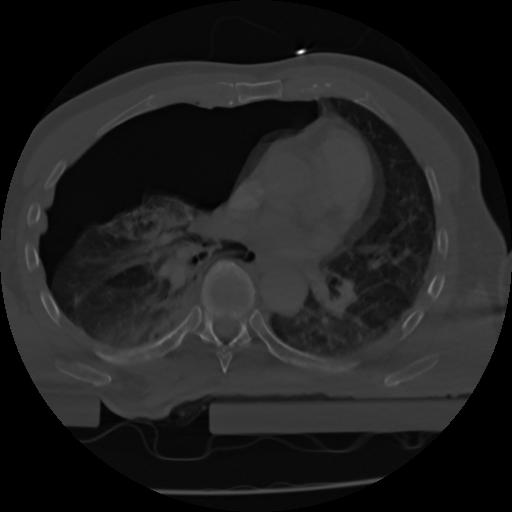

21 ANGIO,CE,Axial,3.0,ANGIO,,